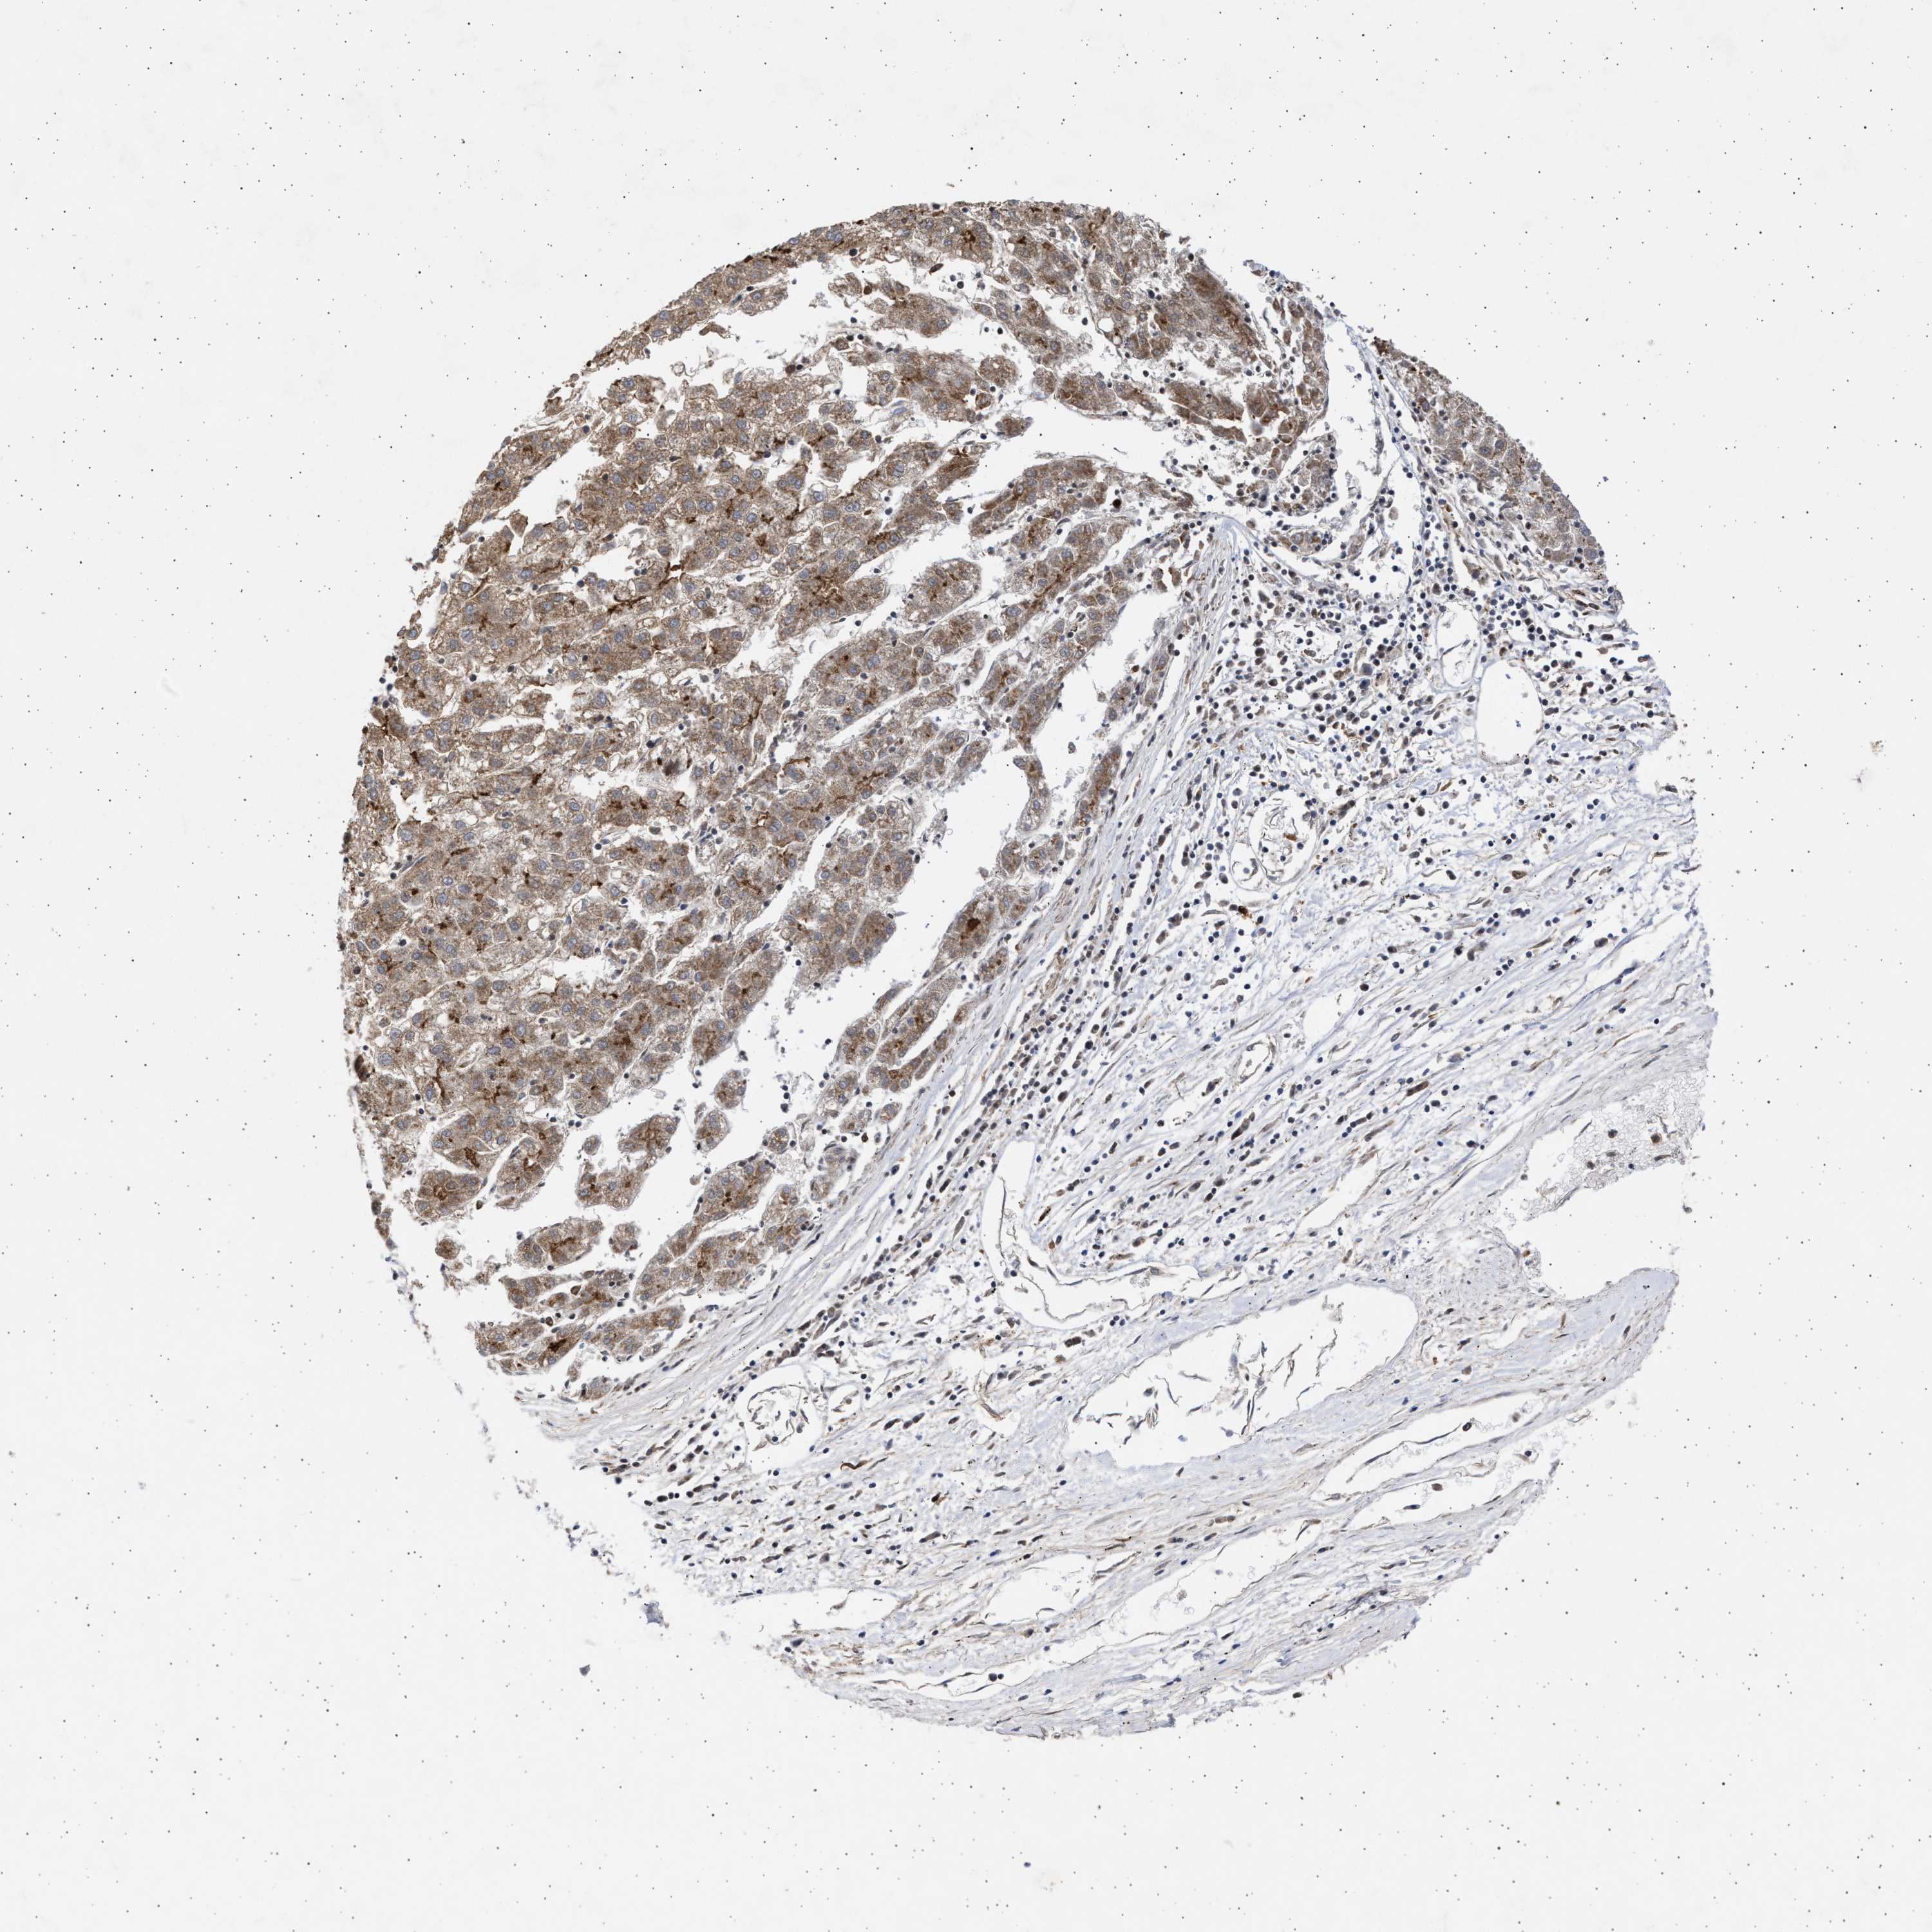

LIVER CANCER - Protein expressioni

A mouse-over function shows sample information and annotation data. Click on an image to view it in a full screen mode. Samples can be filtered based on level of antibody staining by selecting one or several of the following categories: high, medium, low and not detected. The assay and annotation is described here.

Note that samples used for immunohistochemistry by the Human Protein Atlas do not correspond to samples in the TCGA dataset.

Antibody stainingi

Antibody staining in the annotated cell types in the current human tissue is reported as not detected, low, medium, or high, based on conventional immunohistochemistry profiling in selected tissues. This score is based on the combination of the staining intensity and fraction of stained cells.

Each image is clickable and will lead to virtual microscopy that enables deeper exploration of all samples and also displays staining intensity scores, fraction scores and subcellular localization as well as patient and tissue information for each sample.

Antibody HPA023010

Antibody HPA052380

Staining

High

Medium

Low

Not detected

Intensity

Strong

Moderate

Weak

Negative

Quantity

>75%

75%-25%

<25%

None

Location

Nuclear

Cytoplasmic/membranous

Cytoplasmic/membranous,nuclear

Cholangiocarcinoma

Carcinoma, Hepatocellular, NOS